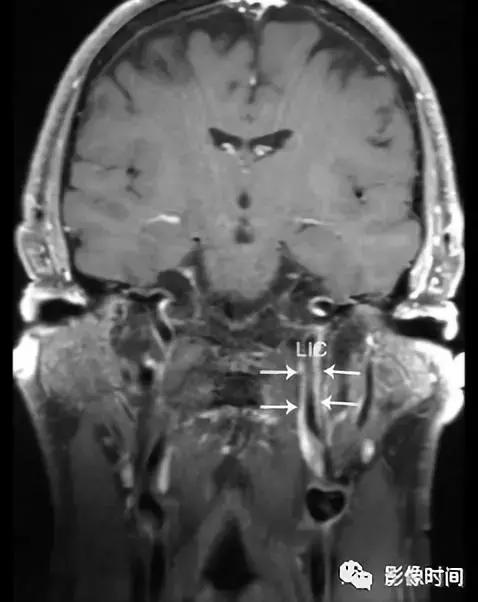

轴位 T1WI+C 显示不均匀强化肿块,完全包裹左侧颈内 (LIC) 和颈外动脉 (LEC)。注意左侧颈内动脉的管腔与右侧颈内动脉 (RIC) 的管径一致。